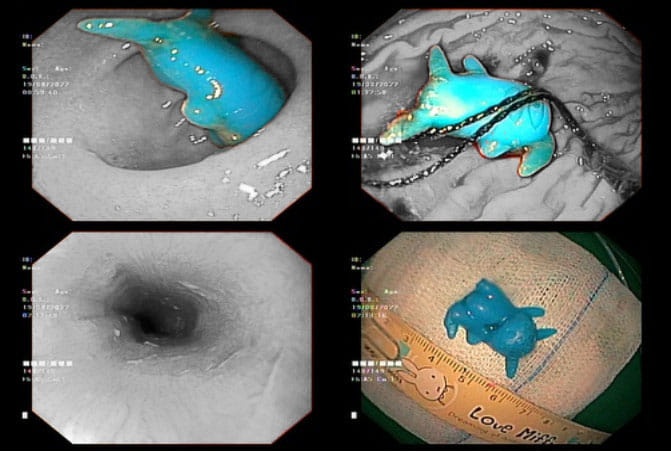

Bác sĩ Võ Hoàng Khoa, khoa Tiêu hóa, cho biết đây là món đồ chơi hình Pikachu bằng nhựa, có kích thước 2x2,5x1 cm. Đồ chơi được phát hiện kẹt ở 1/3 giữa thực quản, có sừng dài, dễ đâm thủng thực quản của trẻ.

Hình ảnh nội soi thực quản của bệnh nhi có đồ chơi hình Pikachu. Ảnh: BVCC.

Tại đây, bé được chẩn đoán theo dõi dị vật kẹt thực quản. Sau khi nội soi cấp cứu trong đêm, món đồ chơi đã được lấy ra ngoài. Sức khỏe của bệnh nhi ổn định.